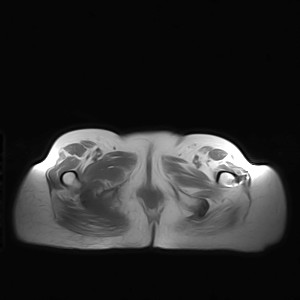

标题: MRI2691:读片病例2

我帮传的没看到病史!!!

图像太差了 1、右侧臀肌旁脓肿? 建议增强 2、左侧股骨头坏死并半脱位

1、左侧股骨头坏死并髋关节半脱位;

2、右侧臀肌感染,(可能褥疮所致)